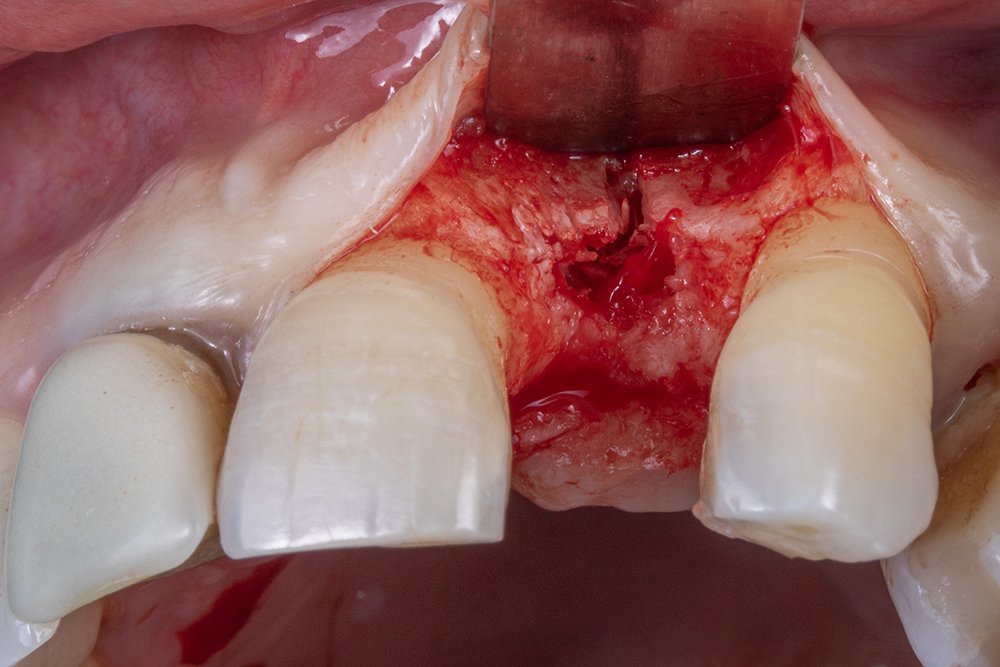

Após realizar a perfuração óssea, utilizou-se o túnel check para mensurar as perfurações e o paralelismo na hora de instalar os implantes.